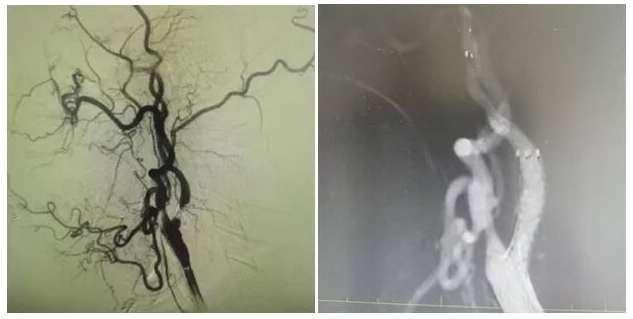

為明確病因,團(tuán)隊為姜大爺安排針對性檢查:頭顱 MRI 彌散成像顯示左側(cè)大腦半球有分水嶺性腦梗死,提示腦組織缺血損傷,頸部 MRA 檢查發(fā)現(xiàn)左側(cè)頸內(nèi)動脈起始處重度狹窄,血流信號減弱。隨后的 DSA(數(shù)字減影血管造影)檢查進(jìn)一步明確,左側(cè)頸內(nèi)動脈起始處狹窄程度超 90%,呈 “閉塞前改變”,血流受阻導(dǎo)致左側(cè)大腦半球供血不足,進(jìn)而引發(fā)腦梗死與抽搐。

手術(shù)當(dāng)天,丁金明主任親自操刀,團(tuán)隊默契配合:在姜大爺右側(cè)腹股溝穿刺股動脈置入動脈鞘,沿鞘送導(dǎo)絲和導(dǎo)管,在 DSA 引導(dǎo)下穿過狹窄部位,用球囊預(yù)擴(kuò)張后,精準(zhǔn)釋放頸動脈支架。術(shù)后 DSA 顯示左側(cè)頸內(nèi)動脈血流通暢,狹窄解除。手術(shù)歷時 1 小時,姜大爺生命體征平穩(wěn),無并發(fā)癥。